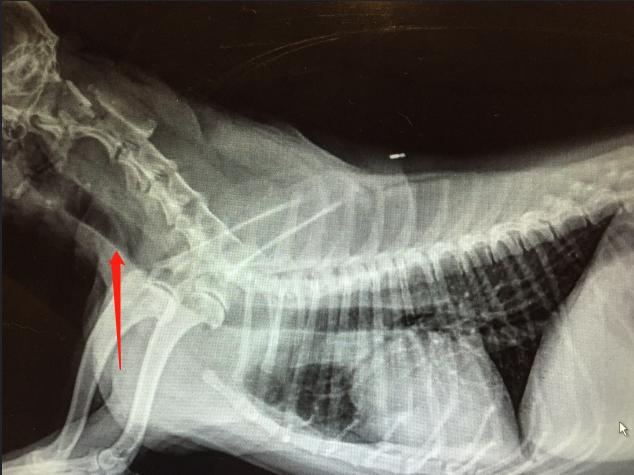

气管X光片

X光片是最常用的方法。主要拍颈部、胸部侧位、腹背位为主。如果在图像上看到气管变狭窄,则可以进行诊断。

但像X光片方法基本可以轻易看出问题在何处。

影像检查结果